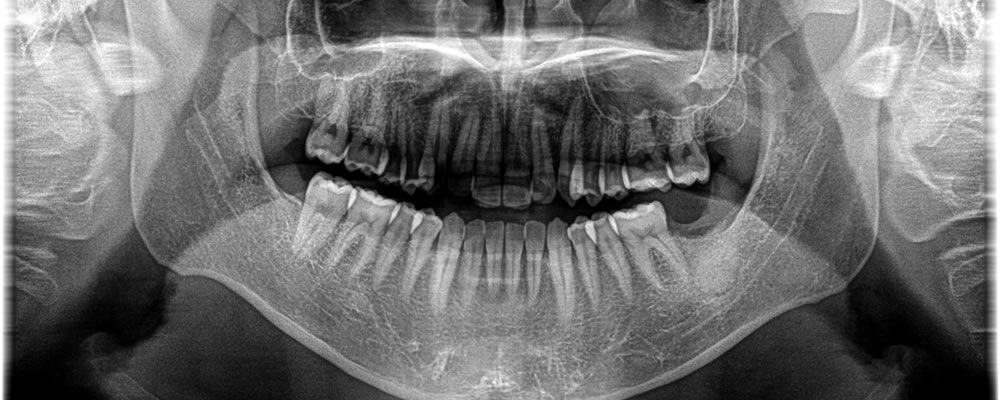

骨が無くなってしまっている部分が下歯槽神経までいってしまっていたため、まずは抜歯と同時に骨を作る処置のみを行い、5ヵ月して骨ができているのを確認した後にインプラントを埋入を行いました。